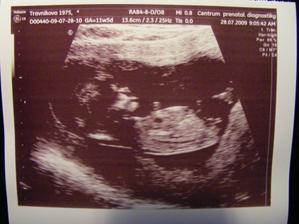

28.7.09v Prenatalu na NT screeningu- NT 2.1mm (coz je nad hranici, ktera je 2), to nas vydesilo. Ale v kombinaci s krvi se to zda OK, riziko 1/570- sice minulych hodnot u Tobika to nedosahuje (1/21000),ale uklidnilo me to. celkove screening negativni, doporucen UZV za 14 dni, prip. genet. konzultace vzhledem k veku. Jinak je to obrik a odpovida 13+1, delka od hlavicky po zadecek 66mm.

8.7.09 1. navsteva u dr., tehu potvrzeno, stanoven termin porodu- 11.2.2009, dostali jsme fotecku dvoucm. rostaka🙂